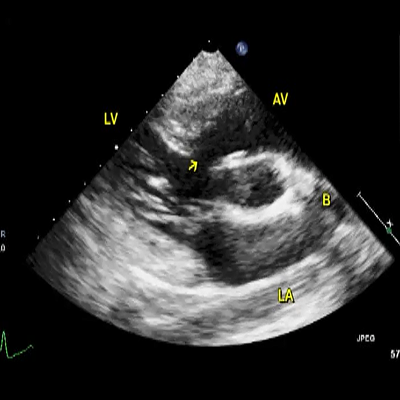

LVO-RA shunt (S) just beneath the TV